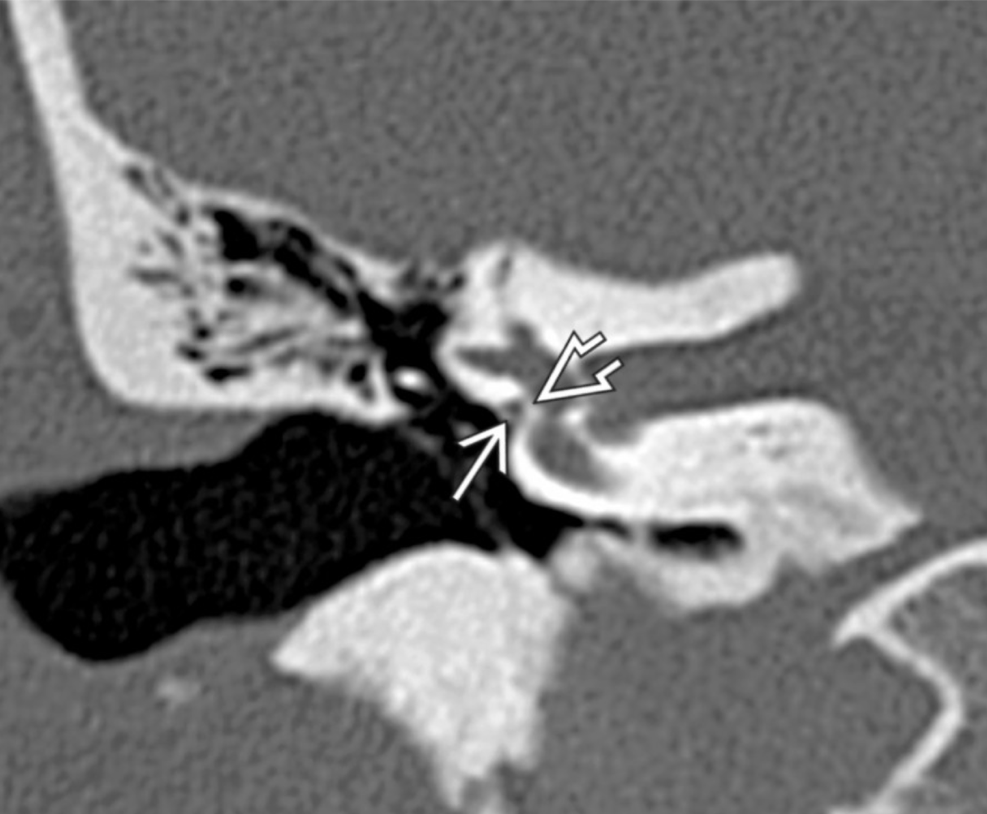

**Tympanic segment of the facial nerve will always be aberrant in the location of the oval window instead of inferior to the lateral semi-circular canal

Prolapsing facial nerve (protruding intratemporal facial nerve)

Tubular soft tissue prolapsing into oval window niche from undersurface of LSC. Caused by dehiscence of bony covering of the facial nerve.

No enhancement! If enhances then it is a Schwannoma.

May project into oval indow.